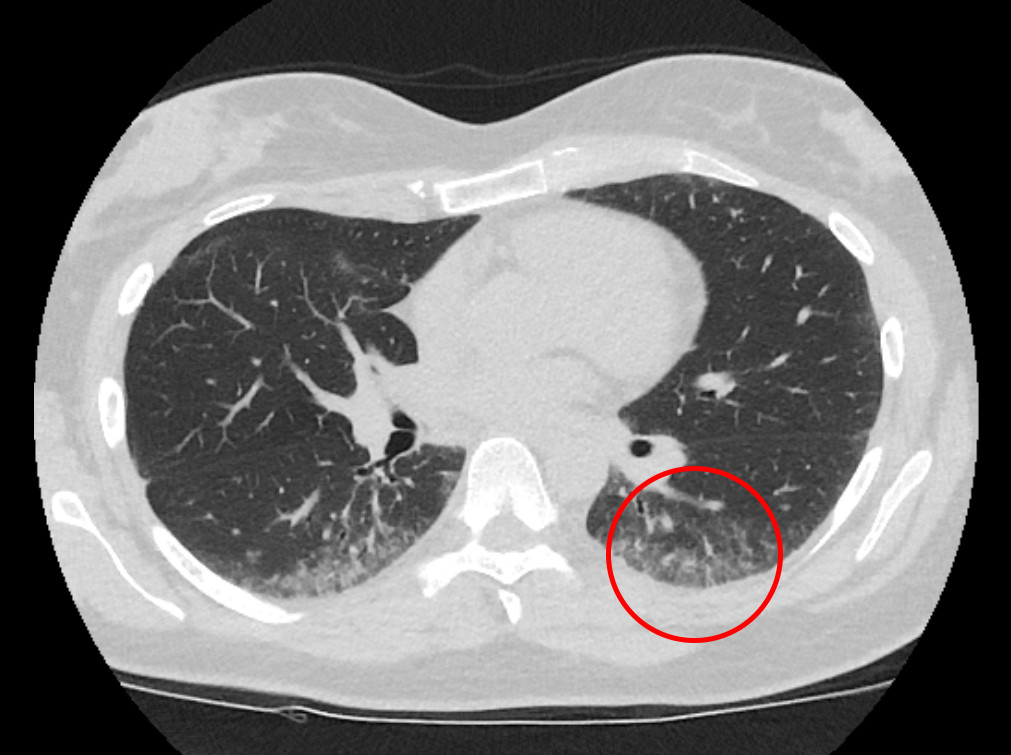

To uker senere ble hun utredet ved lungeavdeling. Ved undersøkelse hadde hun ubesværet respirasjon i hvile. Spirometri bekreftet nedsatt FVK 2,1 l (52 %), FEV1 2,0 l (54 %) og lett økt FEV1/FVK 0,9. Måling av gassdiffusjon viste redusert diffusjon av karbonmonoksyd (DLCO) 4,7 SI (46 %). Kroppspletysmografi viste kraftig nedsatt total lungekapasitet på 3,1 l (58 %). Ved seks minutters gangtest falt oksygensaturasjonen fra 98 % til 79 %. CT av lungene viste perifere grovretikulære tegninger som ga mistanke om non-spesifikk interstitiell pneumoni (NSIP) av fibroserende type (figur 1). Ekkokardiografi viste normale hjerteklaffer og trykkforhold med ejeksjonsfraksjon på 55 %. Det ble ikke sett tegn til arytmi ved 24 timers EKG eller ved fem dagers EKG-registrering. Orienterende blodprøver viste hemoglobin 12,9 g/dl (11,7–15,3), senkning 26 mm (1–17). C-reaktivt protein, trombocytter og leukocytter var innen gjeldende referanseområder. Alaninaminotransferase (ALAT) var 54 U/l (10–45 U/l), alkalisk fosfatase (ALP) 52 U/l (35–105) og laktatdehydrogenase (LD) 310 (105–205 U/l). Hun hadde negativ revmatoid faktor (RF), antisykliske citrullinerte peptider (anti-CCP) og antinøytrofilt cytoplasmatisk antistoff (ANCA). Antinukleære antistoffer (ANA) var svakt positive, men med negative undergrupper.

Utredning av pasientens dyspné viste uttalt restriktiv ventilasjonsinnskrenkning med redusert gassdiffusjon og signifikant desaturasjon ved aktivitet. CT-undersøkelsen av lungene tydet på non-spesifikk interstitiell pneumoni. Hovedsymptomer ved denne tilstanden, som kan være sekundær til bindevevssykdom, er dyspné og tørrhoste, og ved lungefunksjonstester finnes restriktiv ventilasjonsinnskrenkning og redusert gassdiffusjon (2, 3). Pasienten hadde lett forhøyet senkning som ble oppfattet som uspesifikk. Med unntak av forhøyet LD var orienterende blodprøver upåfallende. Revmaserologi viste svak positiv reaksjon på antinukleære antistoffer, men uten påvisning av mer spesifikke antistoffer assosiert med revmatisk sykdom. Hjerteundersøkelsen var uten tegn til arytmi, klaffefeil eller pulmonal hypertensjon. Siden pasientens kliniske funn med ikke-spesifikk interstitiell pneumoni, Raynauds fenomener og positive antinukleære antistoffer kunne være assosiert med bindevevssykdom, valgte man å avvente resultatet av revmatologisk utredning.